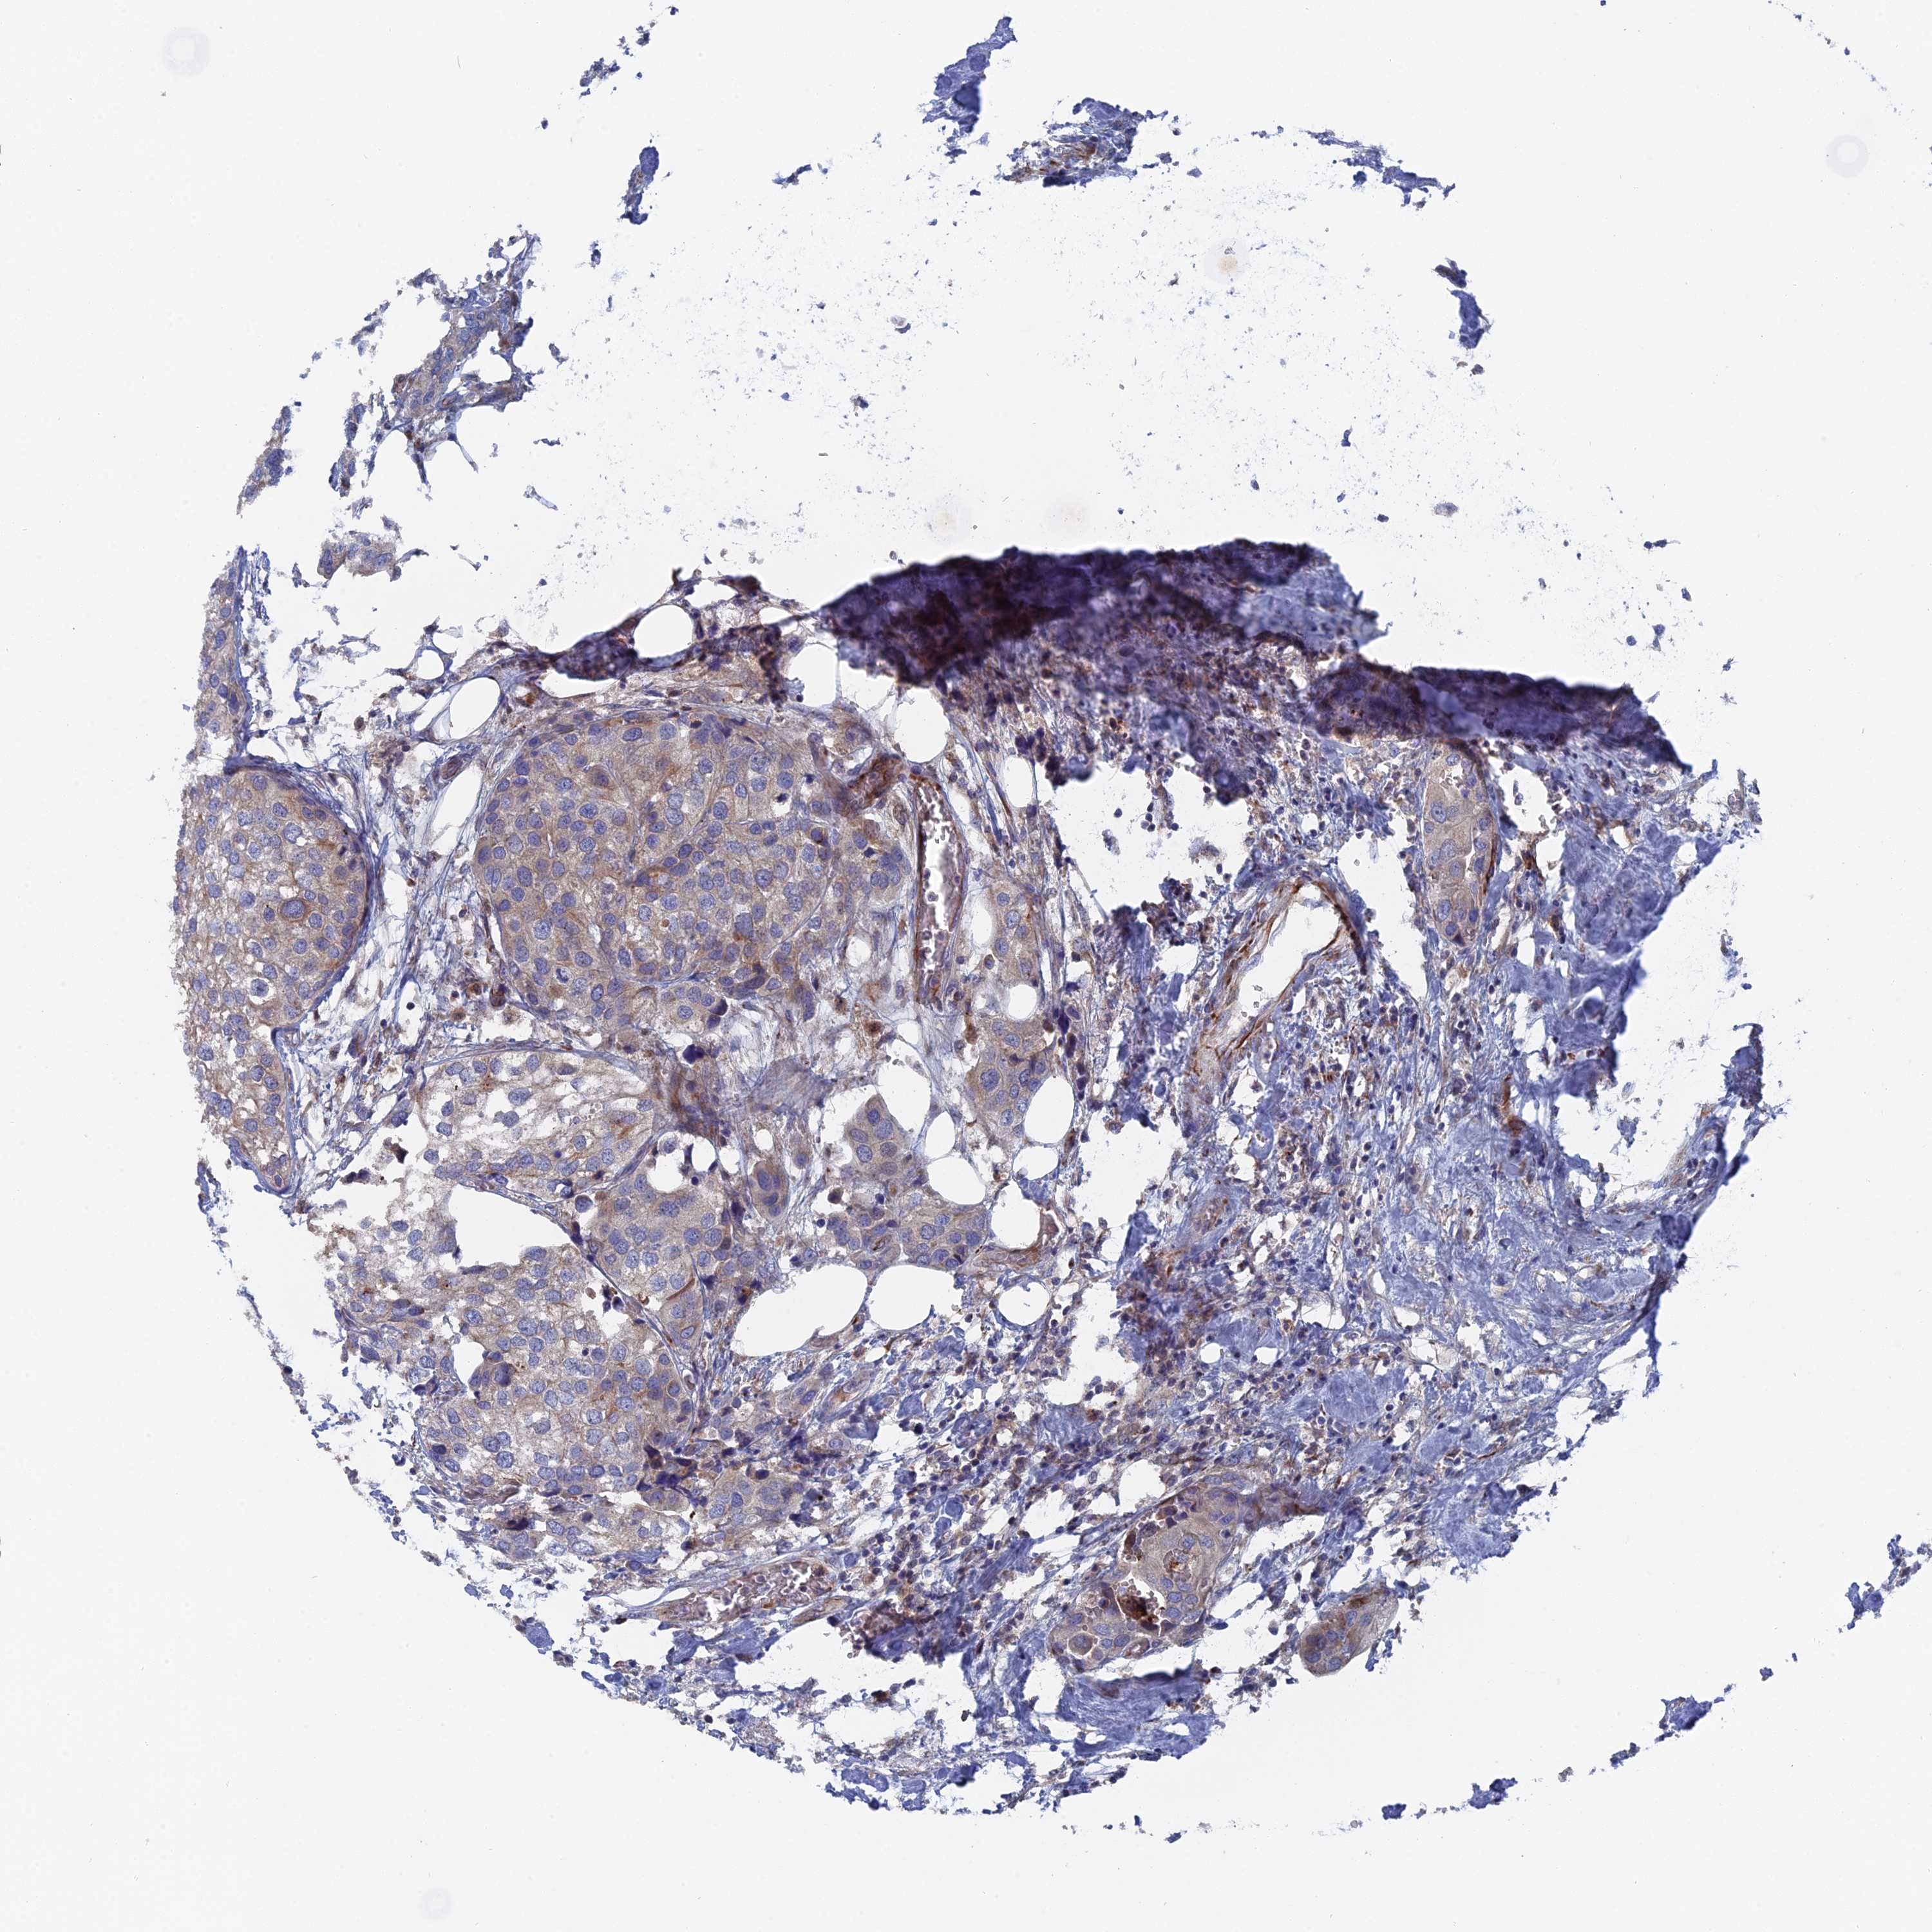

UROTHELIAL CANCER - Protein expressioni

A mouse-over function shows sample information and annotation data. Click on an image to view it in a full screen mode. Samples can be filtered based on level of antibody staining by selecting one or several of the following categories: high, medium, low and not detected. The assay and annotation is described here.

Note that samples used for immunohistochemistry by the Human Protein Atlas do not correspond to samples in the TCGA dataset.

Antibody stainingi

Antibody staining in the annotated cell types in the current human tissue is reported as not detected, low, medium, or high, based on conventional immunohistochemistry profiling in selected tissues. This score is based on the combination of the staining intensity and fraction of stained cells.

Each image is clickable and will lead to virtual microscopy that enables deeper exploration of all samples and also displays staining intensity scores, fraction scores and subcellular localization as well as patient and tissue information for each sample.

Antibody HPA041763

Antibody HPA042096

Urothelial carcinoma, Low grade

Urothelial carcinoma, High grade